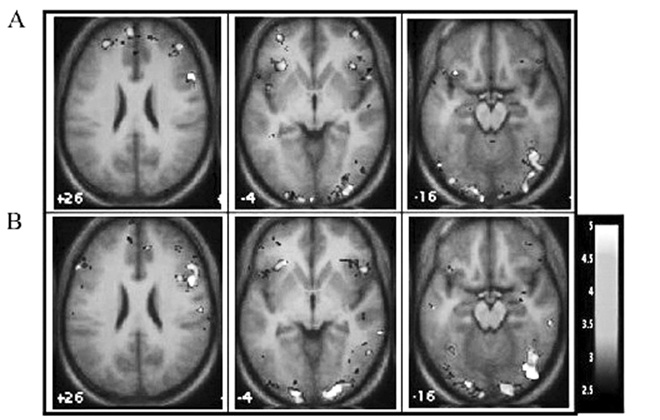

Аналогичную работу по идентификации выражений лица проводили Хизер Гордон и ее сотрудники в Центре когнитивной неврологии, в Дартмутском колледже. В процессе распознавания эмоций (участники которого должны были придавать своему лицу те же выражения, что поочередно появлялись перед ними на экране компьютера) Гордон сравнивала высокие и низкие значения маркеров по Методу исследования психопатической личности (МИЛ) – тесту, как мы уже знаем, разработанному специально для выявления преклинических психопатических черт у населения в целом. Затем с помощью фМРТ она изучала то, что при этом происходило в их мозгу. Обнаруженное ею оказалось весьма необычным и интересным. У тех, кто при тестировании выдал высокие результаты, активность мозжечковой миндалины снижалась по сравнению с теми, чьи результаты были ниже (что вполне согласуется с дефицитом в обработке эмоций по «горячим следам»), зато активность и зрительной, и дорсолатеральной зон префронтальной коры – повышалась. Это, как отмечают Гордон с коллегами, указывает на то, что «участники с высокими результатами, дабы выполнить поставленную перед ними задачу распознавания эмоций, задействовали области, связанные с восприятием и познанием» (рис. 7.1). Но еще интереснее стало, когда Гордон и ее команда, занявшись точностью распознавания… не выявили ничего. В отличие от паттернов активности головного мозга, здесь не нашлось ярко выраженных различий между высокими и низкими значениями маркеров по психопатическим чертам, а это дает веские основания предполагать, что прекрасно срабатывала любая стратегия, какую бы психопаты ни использовали случайно для расшифровки предъявленных им эмоций. ![]() Правая часть дорсолатеральной префронтальной коры Правая часть нижней лобной извилины Зрительная зона Рис. 7.1. Активность в зависимости от уровня оксигенации крови во время распознавания эмоций относительно базового уровня. (A) Участники, показавшие результаты ниже средних на PPL. (B) Участники, показавшие результаты выше средних на PPL. Картинки, представленные в неврологической ориентации: левая часть картинки соответствует левому полушарию мозга (по Гордон и др., 2004) Саймон Барон-Коэн, психолог, профессор Кембриджского университета, пошел дальше. В его тесте «Распознавание эмоций по выражению глаз» («Reading the Mind in the Eyes») требуется рассмотреть фотографии глаз и на основе только этой визуальной информации охарактеризовать психическое состояние человека на фото (см. рис. 7.2). ![]() ![]() ![]() Рис. 7.2. Тест «Распознавание эмоций по выражению глаз» (по Барону-Коэну и др., 2001) Не так легко, как кажется на первый взгляд, верно? Большинство людей крутится в пределах двух из трех (впрочем, я выбрал уж точно не самые простые примеры). Один из трех – и вы успешно справитесь с ним (варианты ответов внизу страницы [53] ). Тест «Распознавание эмоций по выражению глаз», как вы уже, вероятно, поняли, представляет собой прекрасный пример полного отсутствия сопереживания – в противоположность горячему сочувствию, о чем мы только что говорили. Участники, в конце концов, не обязаны испытывать эмоцию, изображенную на картинках. Они должны ее просто распознавать. А вот Барону-Коэну в голову пришла блестящая идея. Он спрашивал себя, как – в сравнении со всеми нами – психопатам удается проходить тест? В свете предыдущих результатов нейровизуализации (томографии головного мозга) можно было бы предположить, что у психопатов результаты должны практически ничем не отличаться от результатов остальных людей. |